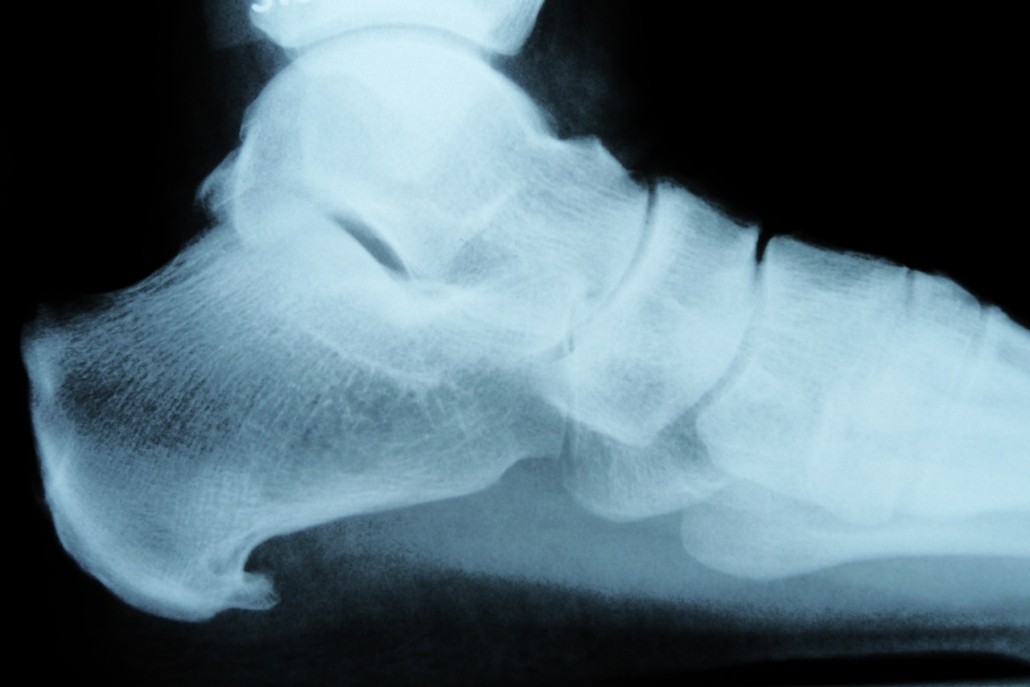

Een hielspoor is een klein aangroeisel aan de voor- en onderzijde van de hiel. Het ontstaat door jarenlang staan, lopen en springen. De platte peesplaat onder de voet ook wel de ‘fascia plantaris’ genoemd trekt jarenlang aan de hiel, waardoor de hiel soms de neiging heeft om extra bot aan te maken. Hierdoor ontstaat een soort aangroeisel de zogenaamde ‘hielspoor’. Deze is goed zichtbaar op een röntgenfoto.

Sinds een jaar of tien geleden echografie zijn intrede deed binnen de fysiotherapie kon deze platte peesplaat zelf ook bekeken worden en al snel bleek dat het niet de hielspoor (het aangroeisel) maar de overbelaste en verdikte platte peesplaat was die de hielpijn veroorzaakte. Sommige zorgverleners zijn daar niet van op de hoogte en noemen de hielpijn nog altijd ‘hielspoor’, terwijl het in feite om een peesplaatontsteking (fasciitis plantaris) gaat.